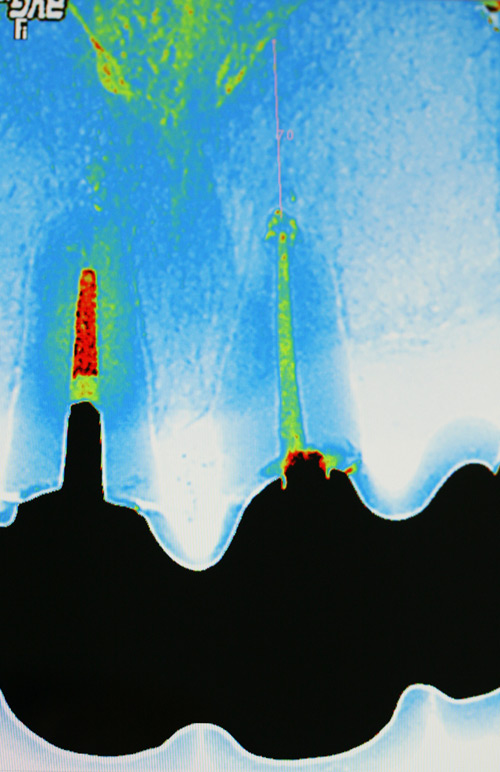

Unsere Praxis ist mit digitalen CCD Röntgensensoren der neuesten Generation ausgestattet. Diese ermöglichen gegenüber der konventionellen zahnärztlichen Röntgentechnik eine Reduktion der Strahlendosis um bis zu 90%. Darüber hinaus sind Auflösung und Kontrastverhalten der Bilder konkurrenzlos. Dies ermöglicht eine extrem schonende und exakte Diagnostik.